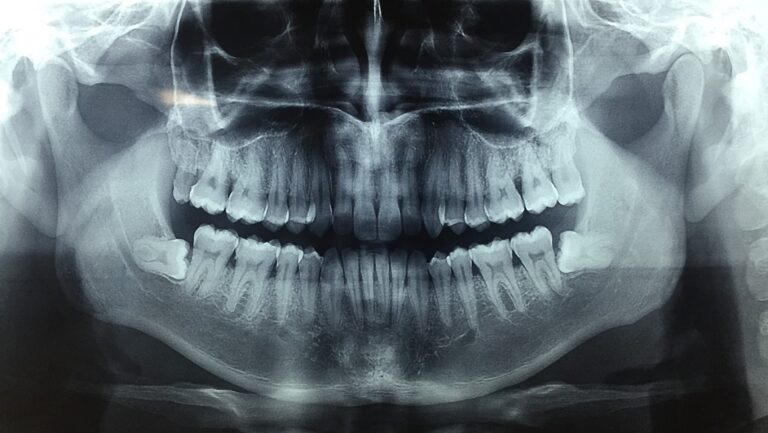

Cirugía de terceros molares o molares del juicio

La cirugía de terceros molares o muelas del juicio es un procedimiento quirúrgico menor que se...